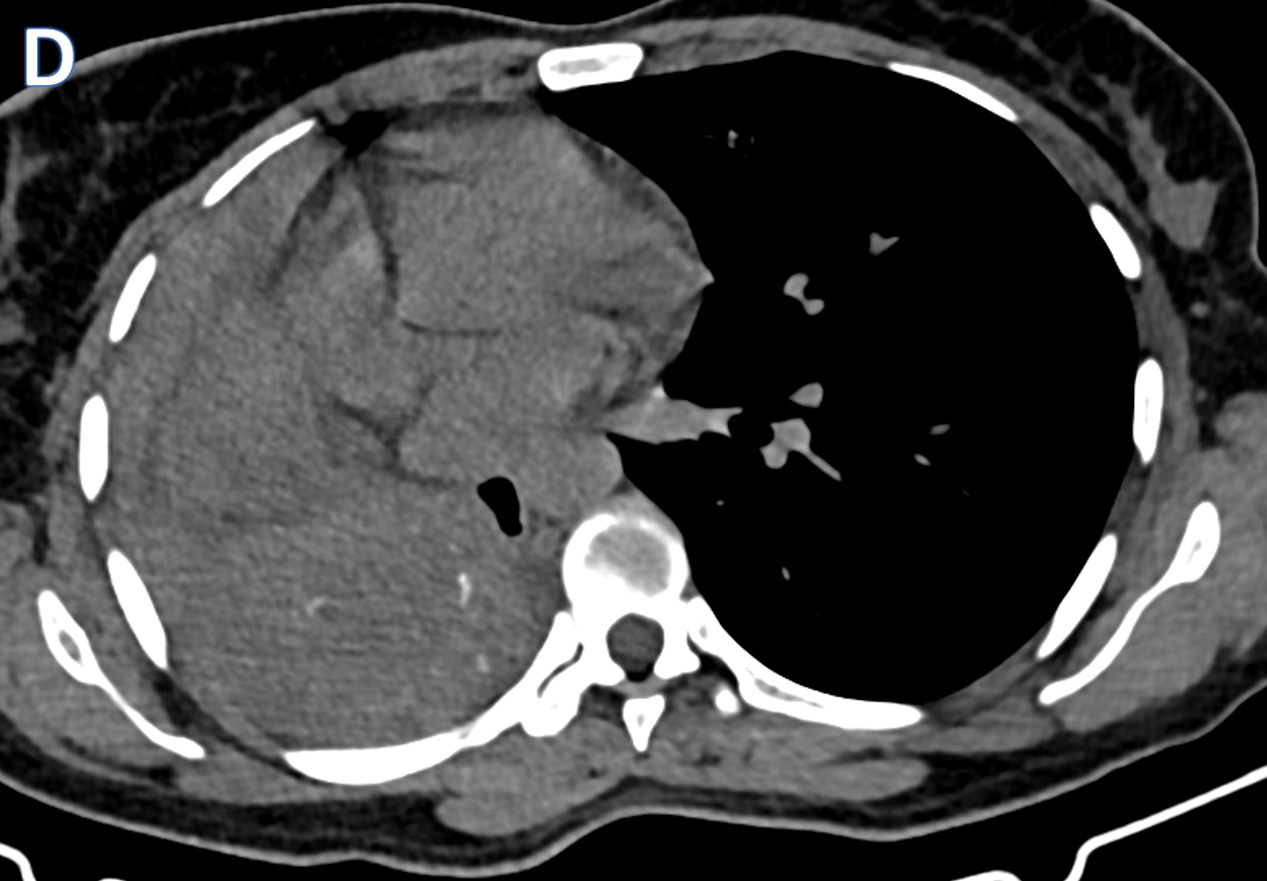

1. Axial MRI images

Shows multiple dilated collaterals in the subcutaneous plane of the thigh along with a prominent and dilated vessel noted in the lateral aspect of the thigh.

3. Venography shows a dilated venous channel running in the lateral aspect of the thigh ( lateral marginal vein of servile) and draining through the accessory medial vein into the profunda femoris ( Type IIa)

Normal deep venous system noted

A small dilated varix is noted.

- Typical angiographic findings, which may also be seen on contrast-enhanced CT-scan or MRI, shows The marginal vein of Servellea pathognomonic finding (a subcutaneous vein found in the lateral calf and thigh)